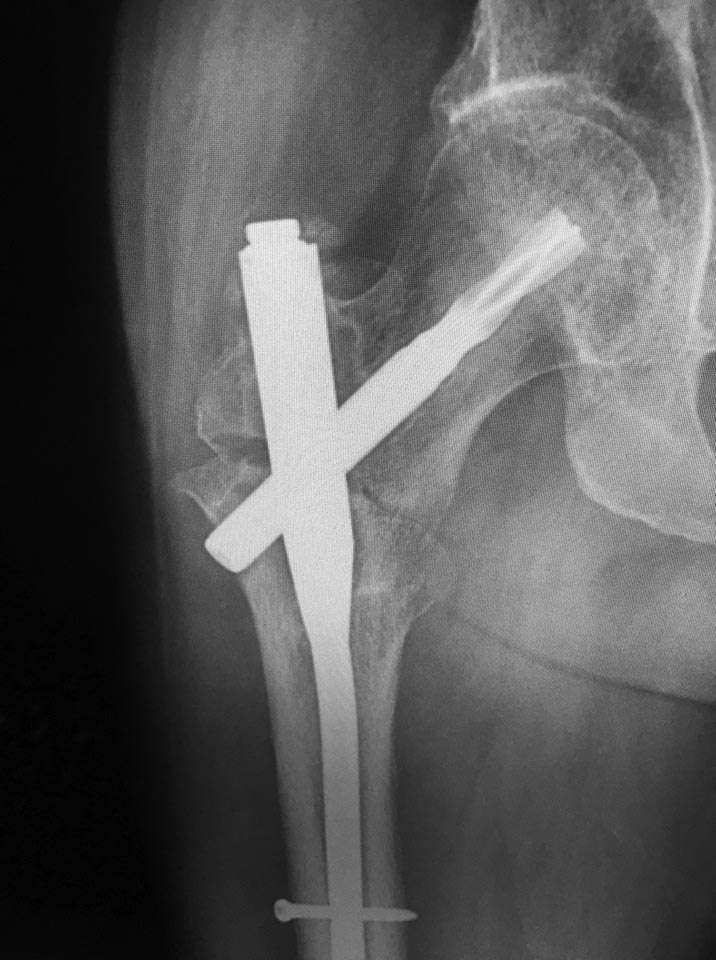

Несращение межвертельного перелома

доброго времени суток! как бы вы поступили в данном случае? Пациент 52 года, синтез 7 мес назад, ходьба с костылями.

Боль при ходьбе. Два дистальных блокируемых винта в статике ( срезалось на фото)

Уважаемый коллега, я бы попробовал реостеосинтез. Взял бы стержень интертан smith nephew, дал компрессию между отломками. В головке достаточно места, лезвие изначально установлено короткое.

Надо сделать notching. То есть вырубить ниже шеечного винта паз в латеральной стенке.

Надо сделать дефект латерального кортекса высотой мм 10-15 шириной в этот винт прямо дистальнее винта, чтобы под ним была не стенка, а дырка. Удалить дистальные винты. И сколотить на столе. И либо оставить без винтов, либо динамический ввести, если есть сильные ожидания ротационной подвижности. Скорее всего, и он не нужен.

Или еще один вариант - заменить клинок на более короткий, и ввести его так, чтобы он латеральнее гвоздя не выстоял. И даже этот, наверно, можно просто поглубже пробить - места в головке хватает.